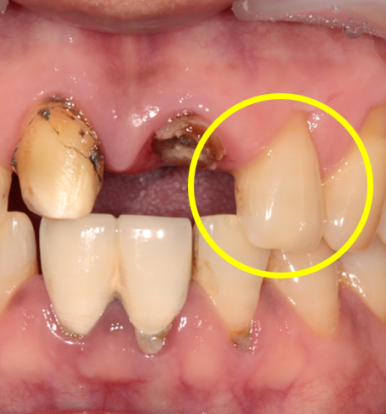

그중 뿌리만 남은 치아의 옆 치아(측절치, #22)도 금이 가있는 것을 발견을 했습니다.

아쉽게도 이 치아에도 금이 가있네요

(맨 우측 사진: 치료 중 X-ray 사진. 치아에 금이 간 것이 선명하게 보입니다.)